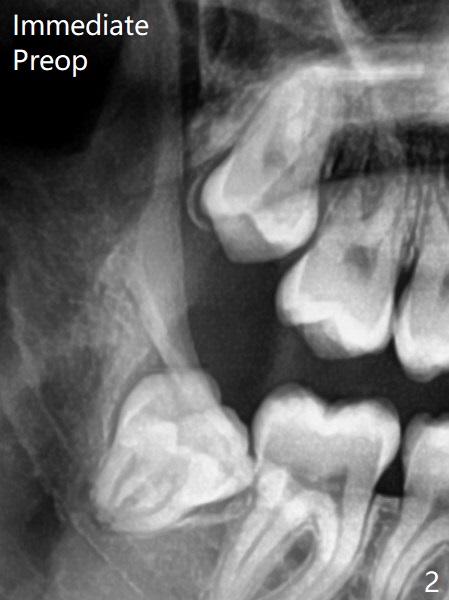

Xin Wei, DDS, PhD, MS 1st edition 11/21/2020, last revision 11/23/2020